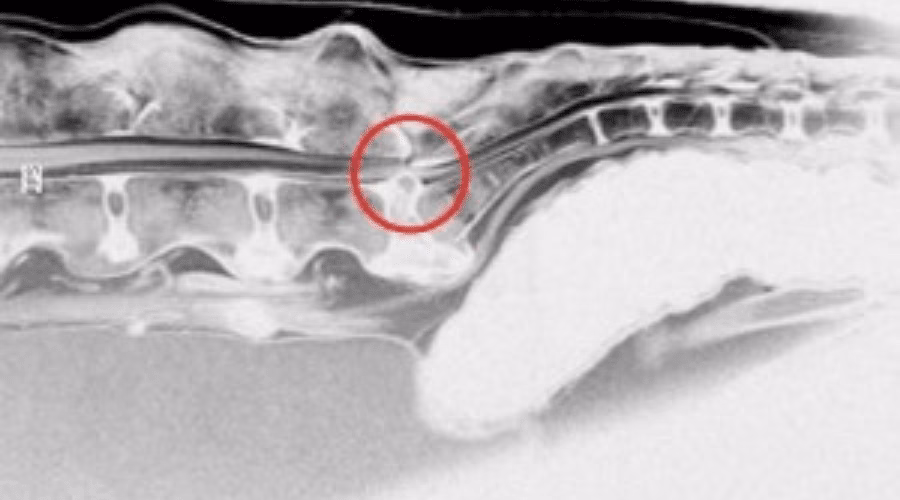

- MR-scanning (Magnetisk Resonans Imaging): Dette anses for at være guldstandarden for diagnosticering af CEKS. En MR-scanning giver detaljerede billeder af både knogler og bløddele og kan præcist vise, hvor og hvorfor nerverne er i klemme.

- CT-scanning (Computertomografi): En CT-scanning er også en avanceret billeddiagnostisk metode, der er særligt god til at vise knoglestrukturer og kan også bruges til at stille diagnosen.

Syndromet opstår, når der er et pres på disse nerver i Cauda Equina. Den hyppigste årsag er degeneration og instabilitet i overgangen mellem den sidste lændehvirvel (L7) og korsbenet (S1). Dette område er den mest bevægelige del af hundens ryg og er derfor særligt udsat for belastning.

- Disk degeneration: Mellem hver ryghvirvel ligger en diskus (båndskive), der fungerer som en stødpude. Med alderen, eller ved intens belastning (f.eks. hos sports- og tjenestehunde), kan denne diskus blive slidt. Den tørrer ud, mister sin elasticitet og kan bule ud i rygmarvskanalen, hvor den trykker direkte på nerverne.